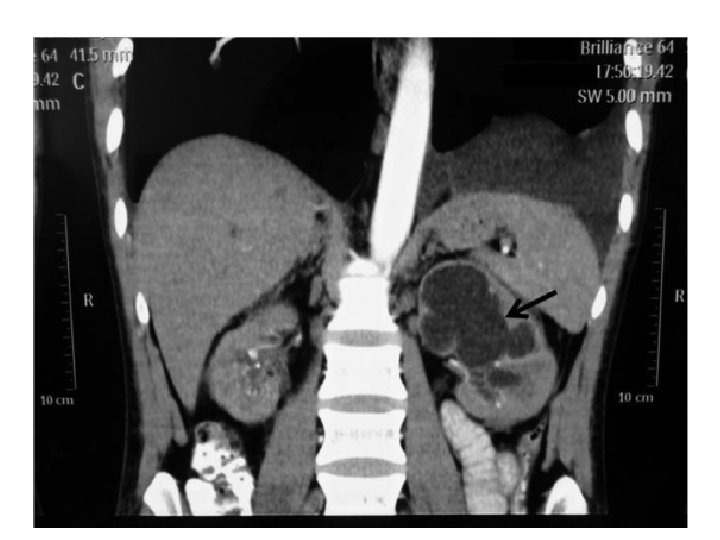

Imagem • RX de tórax: • Velamento de seio costofrênico esquerdo • Ultrassonografia renal: • Rim D pequeno com calcificações • Rim E aumentado, com hidronefrose e redução de parênquima • Solicitadas tomografias de abdome e tórax